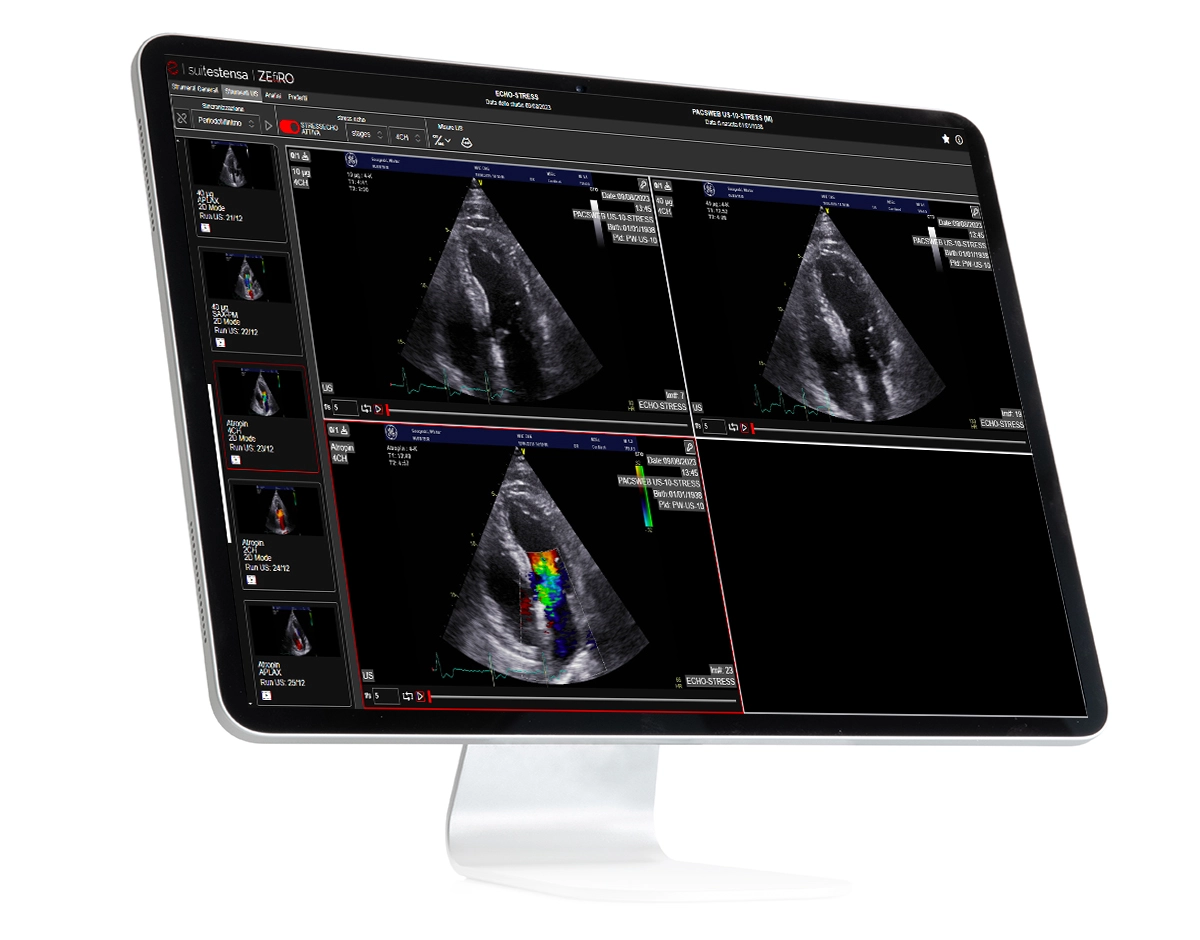

Suitestensa ZEfiRO

Zero-footprint medical imaging PACS software

SUITESTENSA ZEfiRO transforms your cardiology and enterprise imaging workflows with its cutting-edge, cloud-native architecture. Designed with advanced zero-footprint (ZFP) technology, ZEfiRO gives clinicians and operators instant and secure access to diagnostic imaging from any devices, without the need to install any software. Whether you work for a small diagnostic center or for a complex diagnostic imaging network, ZEfiRO adapts seamlessly to meet your needs, leveraging a reach of diagnostic functionality. Experience outstanding performance, scalability, and efficiency in managing diagnostic images like never before.

ZERO-FOOTPRINT TECHNOLOGY: LIGHTWEIGHT INTERFACE AND BROWSER-BASED ACCESS

UNIFIED CLINICAL WORKFLOW ACROSS THE MEDICAL DEPARTMENTS

ALL-IN-ONE SOLUTION: MANAGE ECG, ELECTROPHYSIOLOGY, AND MORE, ALL IN ONE PLATFORM